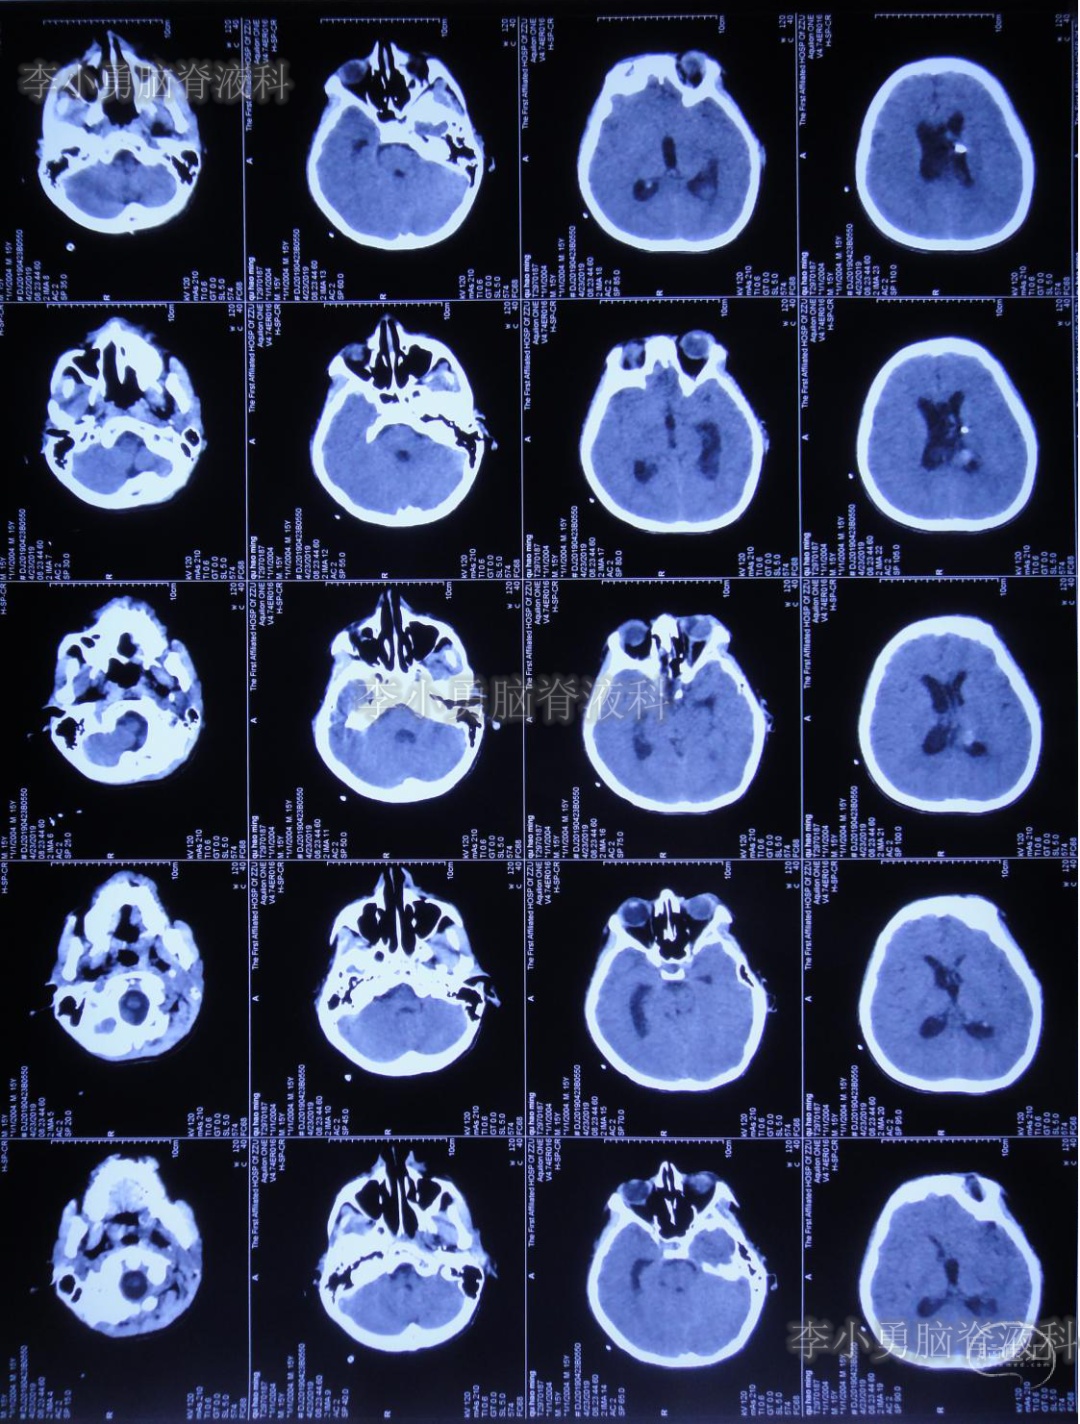

次日2019年4月3日(脑出血后8天),转至河南省郑州市某三甲医院;入院当日头颅CT(图-5)及CTA(图-6)检查结果:出血量较昨日无增加,动脉血管未见明显异常。

图-5:2019年4月3日头颅CT:出血量无增加

图-6:2019年4月3日头颅CTA:未见明显异常

继续给予脑室外引流1周后即2019年4月11日,再次复查头颅CT(图-7):脑室内积血明显减少,脑室不大。

图-7:2019年4月11日头颅CT:脑室内积血明显减少

为明确脑室内出血原因,拔除脑室外引流管1周后即2019年4月18日,行脑血管造影(片子遗失)检查:左侧“脑室内动脉瘤”。

为防止动脉瘤破裂,停止了每日的腰椎穿刺治疗,并积极完善动脉瘤夹闭术前准备。拔除第二次脑室外引流管后12天即2019年4月23日,患者出现哭闹、呕吐、发热及烦躁症状,紧急检查头颅CT(图-8):脑室较前略扩大,未见明显积血。

图-8:2019年4月23日头颅CT:脑室略扩大